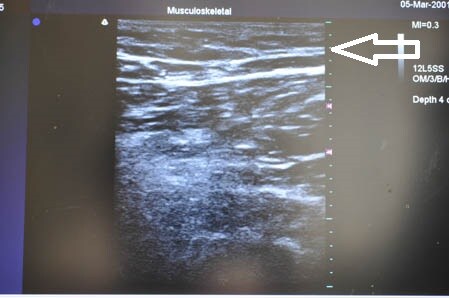

最後に参考までに今回の患者様の

硬膜外麻酔(患者様はこれをたくさんインスタでご覧になったそうです)と

術中の模様を紹介しましょう。